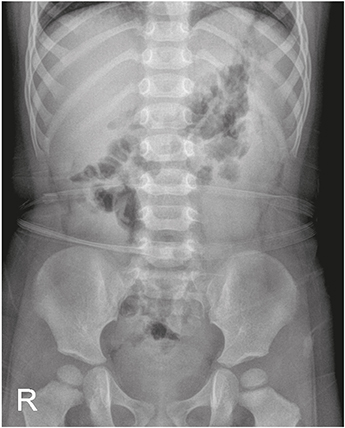

Abdominal radiography showed gaseous distension of the colon (Fig. 1). Laboratory findings included leukocytosis (22.64 k/mm3) with an upper left shift (segment 82.9%), mild anemia (12.5 g/dL), thrombocytosis (456 k/mm3) and decreased serum glucose (65 mg/dL) and sodium (134 mg/dL) levels. Plasma urea and creatinine concentrations, and those of other electrolytes were within normal limits, and C-reactive protein (CRP) was also nearly normal (0.66 mg/dL).

Fig. 1

Simple abdomen radiograph (flat) at the admission.